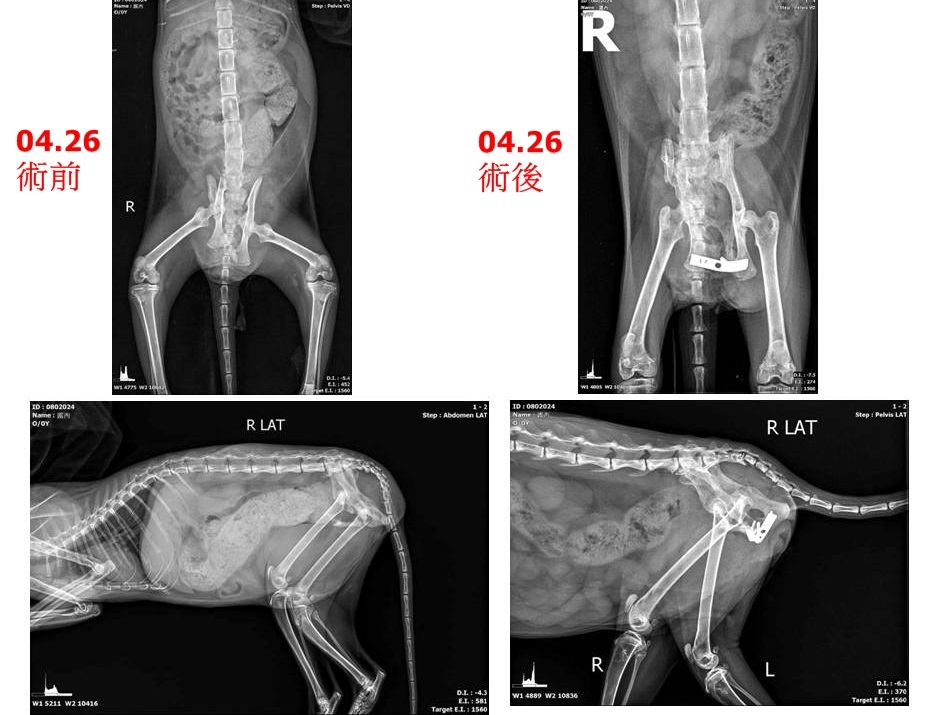

本筆醫助為露西於4月26日至6月11間在沐恩醫院的費用,包含住院、檢驗、骨盆手術、骨折外固定手術、絕育手術,希望關心露西的朋友能夠一起幫忙,謝謝大家。

再至長青進行電腦斷層診斷,以利泌尿道專科醫師進行股盆腔手術。

露西已確定是終身癱瘓、每日須人工擠便尿,並進行骨盆腔擴張手術,才能維持生活品質並以利後續照顧。

在住院二月餘,健康狀況至一定程度穩定後,露西進行了手術並於完成結紮,醫院評估已可出院自行照護,日後再視情形回診追蹤。